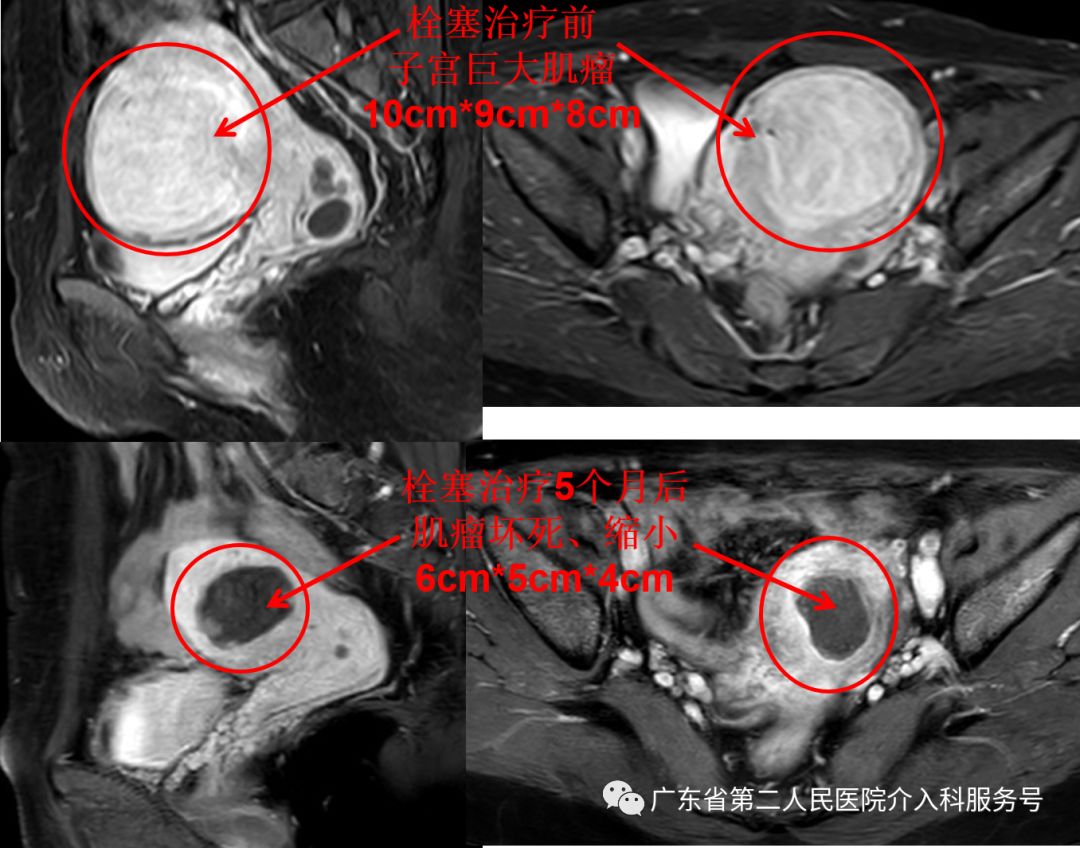

下图为梁女士的磁共振检查:子宫巨大肌瘤(国际妇产科联盟(FIGO)子宫肌瘤Ⅴ型,大小约10m*9cm*8cm)

治疗后差不多1个月,梁女士的“大姨妈”驾到,量正常,第7天即干净,再也没有淋沥不净的尴尬。3个月后,梁女士例假依然正常,已没有贫血貌,现在久坐后站立时再也没有出现眼前发黑(黑蒙)的现象。梁女士高兴的说:终于摆脱“大姨妈”来时排山倒海,大量血块,淋沥不净的烦恼,关键是可以和其他女性一样保留子宫,正常来月经,没有血块,不会淋沥不净,生活也舒坦了。门诊复查血红蛋白在正常范围,磁共振如下(子宫肌瘤已坏死、吸收、缩小(6cm*5cm*4cm),随后坏死的肌瘤还会继续吸收、缩小)。